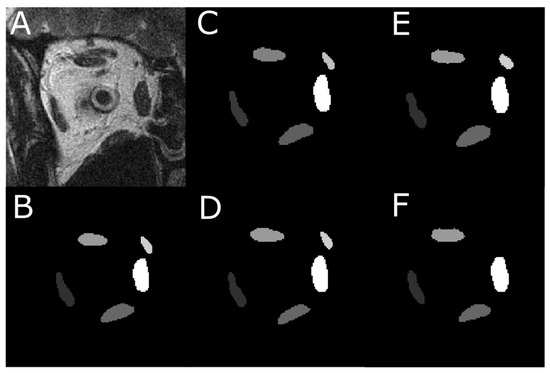

3.1. Assessment of Segmentation Accuracy

3.4. Analysis of T-2 Weighted MRI Images